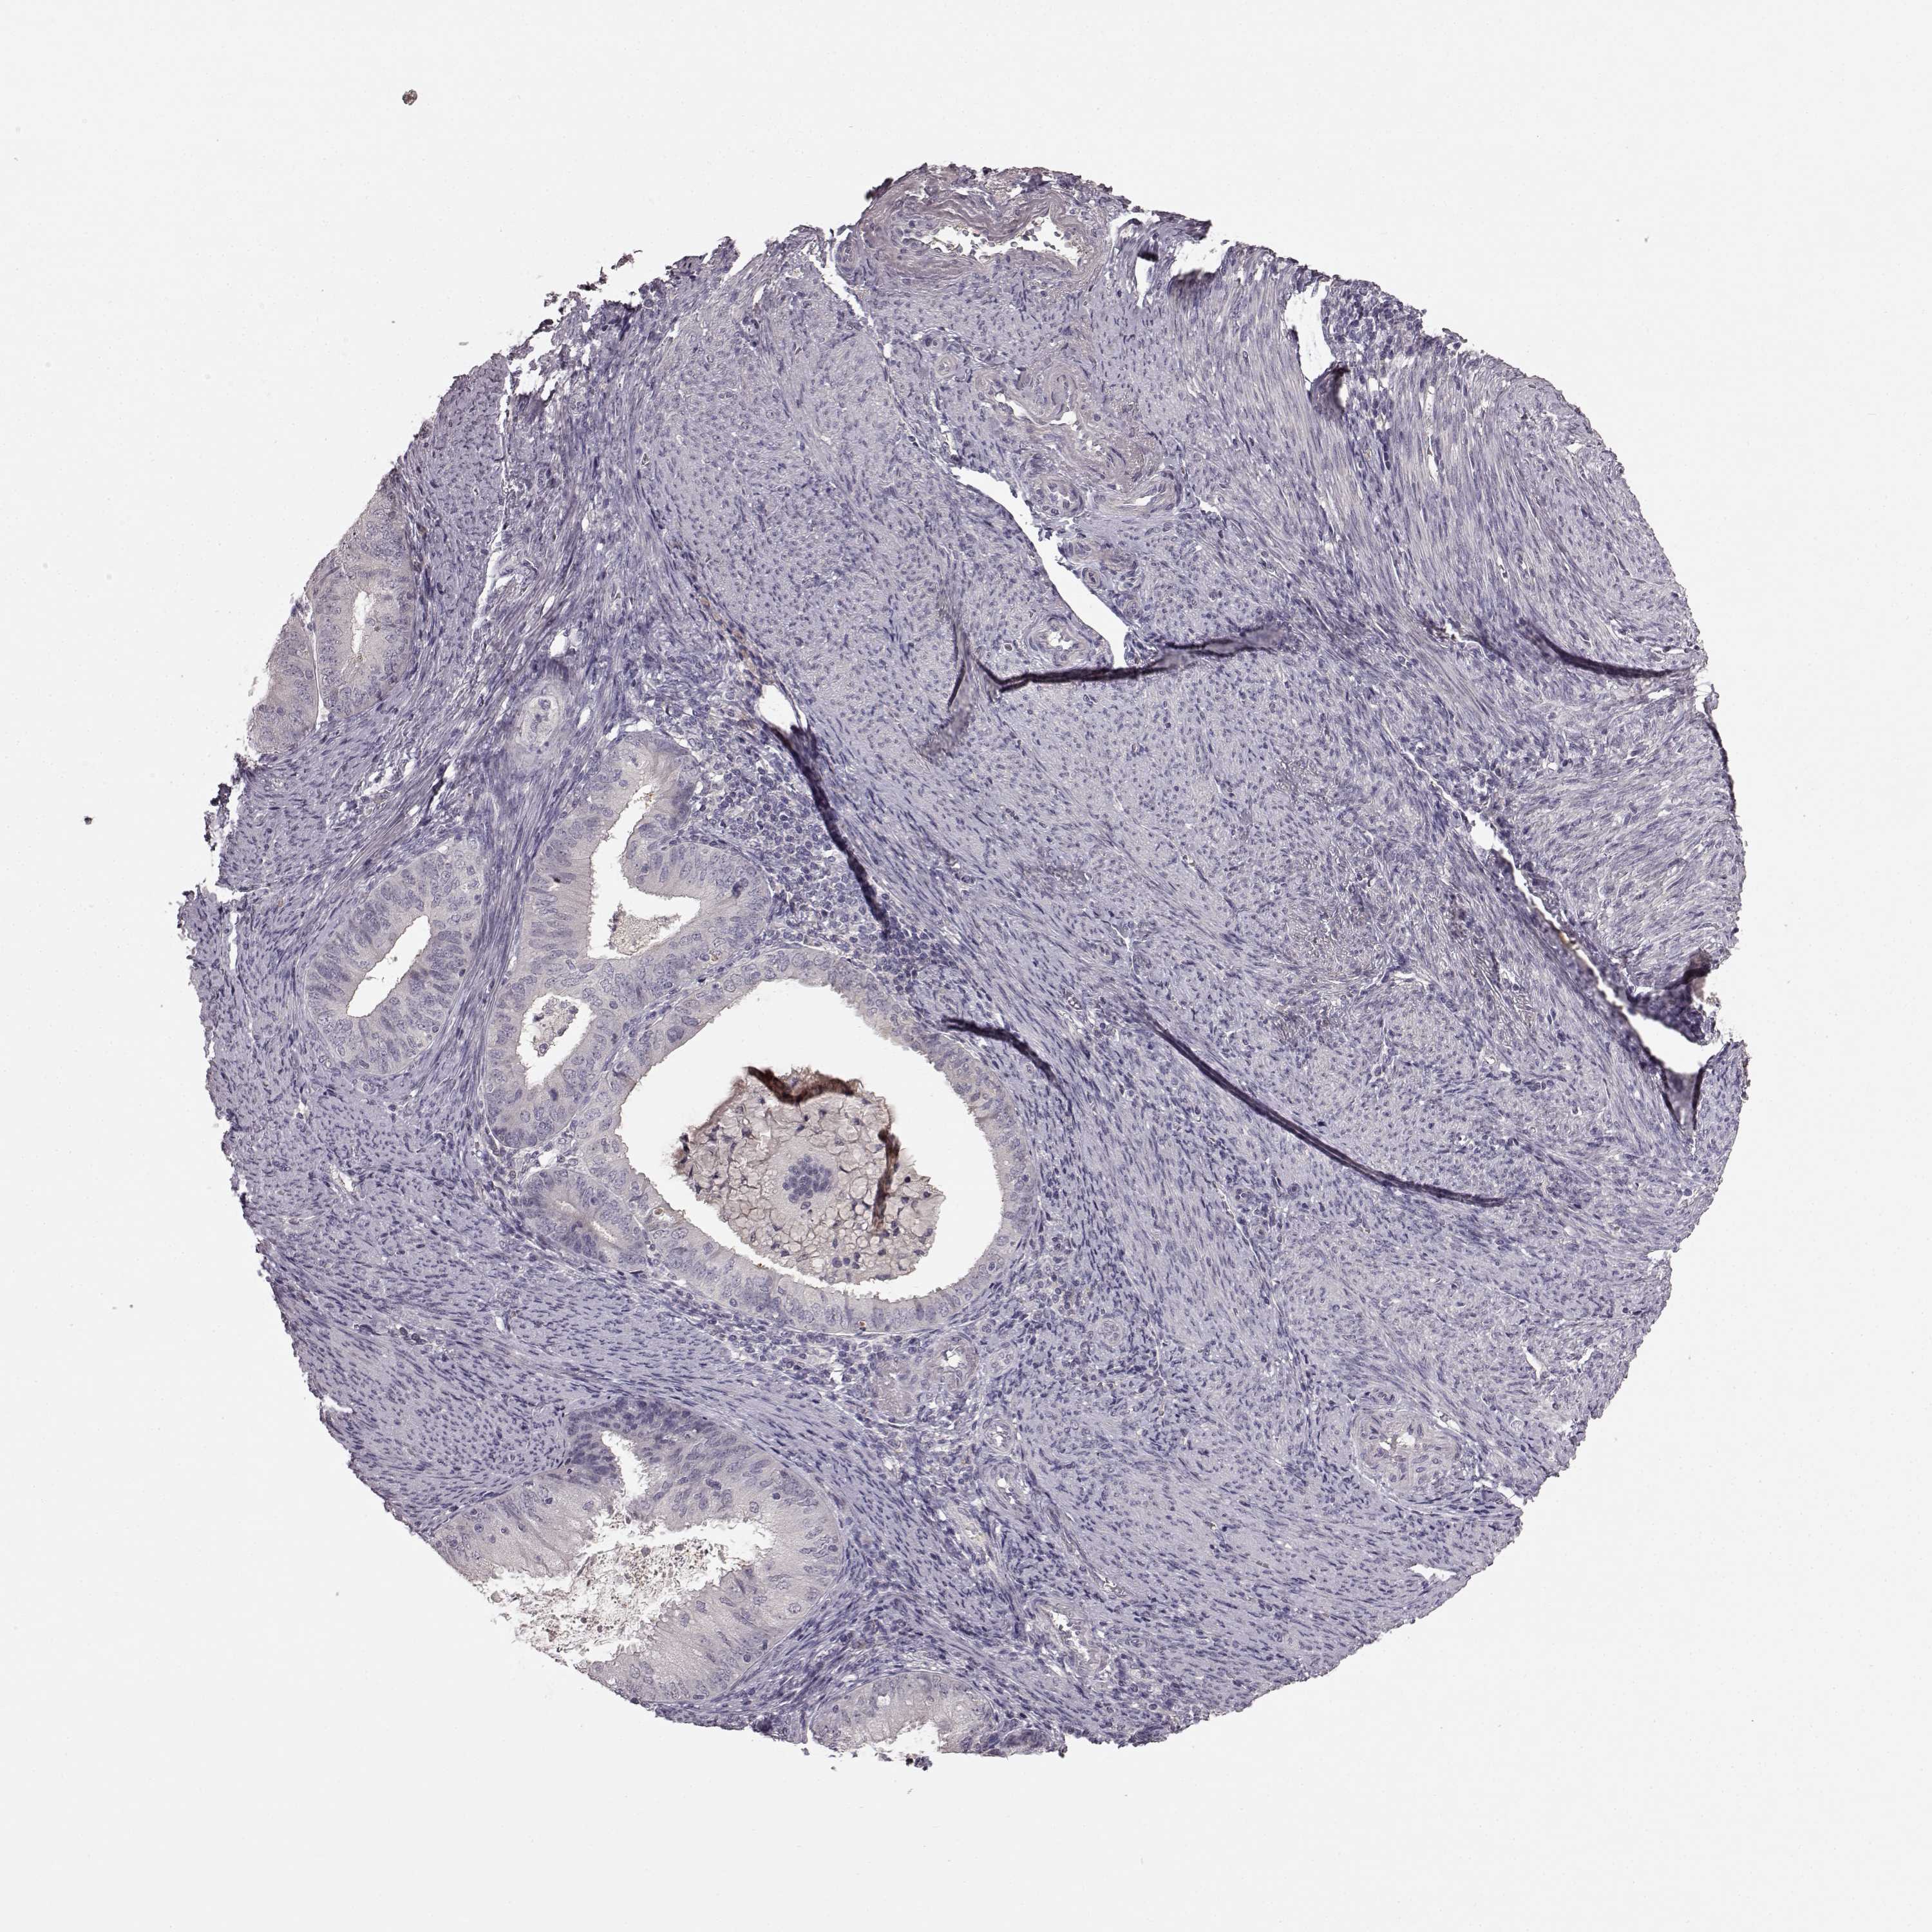

ENDOMETRIAL CANCER - Protein expressioni

A mouse-over function shows sample information and annotation data. Click on an image to view it in a full screen mode. Samples can be filtered based on level of antibody staining by selecting one or several of the following categories: high, medium, low and not detected. The assay and annotation is described here.

Note that samples used for immunohistochemistry by the Human Protein Atlas do not correspond to samples in the TCGA dataset.

Antibody stainingi

Antibody staining in the annotated cell types in the current human tissue is reported as not detected, low, medium, or high, based on conventional immunohistochemistry profiling in selected tissues. This score is based on the combination of the staining intensity and fraction of stained cells.

Each image is clickable and will lead to virtual microscopy that enables deeper exploration of all samples and also displays staining intensity scores, fraction scores and subcellular localization as well as patient and tissue information for each sample.

Antibody HPA067812

Antibody HPA071461

Staining

High

Medium

Low

Not detected

Intensity

Strong

Moderate

Weak

Negative

Quantity

>75%

75%-25%

<25%

None

Location

Nuclear

Cytoplasmic/membranous

Cytoplasmic/membranous,nuclear

Adenocarcinoma, NOS